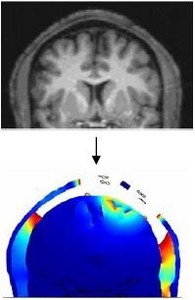

We calculated the spatial distribution of the electric fields induced in the brain during transcranial current stimulation (TCS). The spatial focality obtained using ‘concentric-ring’ configurations is investigated using a realistic MRI derived 3D finite element model of the human head.

Two disc electrode configurations were simulated using COMSOL Multiphysics. The distant-bipolar configuration, which is comparable to commonly used TCS protocols, resulted in diffuse (un-focal) modulation. The reduced concentric-ring results in higher spatial focality at the expense of increased total surface current. Superficial cortical neurons may be thus selectively targeted using a concentric-ring configuration.